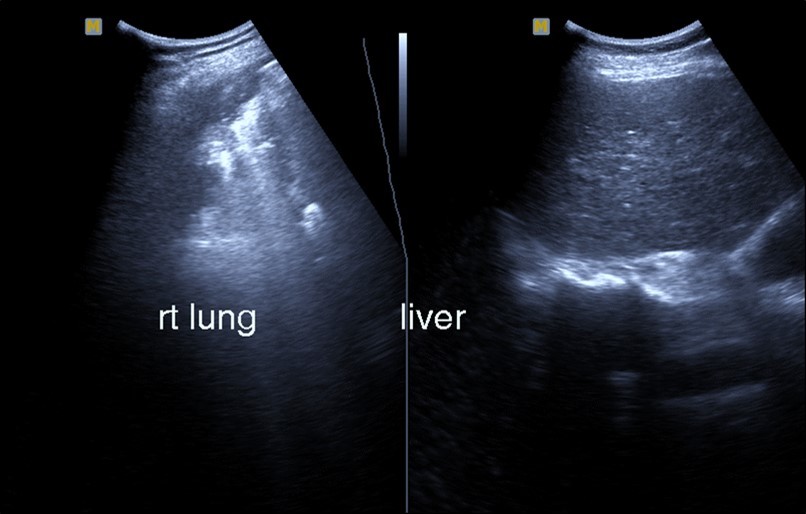

Bed side chest ultrasound may reveal positive findings as multiple Kerley’s B lines (>3 per intercostal space), pleural wall thickening (Figure 1), patchy areas of pulmonary consolidations especially in subpleural location (Figure 2, Figure 3) and obstructive lung collapse.

Figure 2.Chest ultrasound showing subpleural consolidation in patient with Covid-19.

Figure 3.Chest ultrasound showing right lung segmental consolidation with positive air bronchogram.